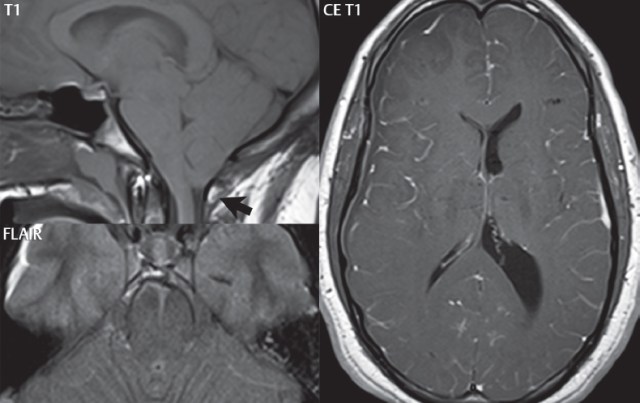

Uncal Herniation is a subtype of transtentorial downward brain herniation involving the uncus. It occurs when there is a certain increase in intracranial pressure. This rise in intracranial pressure causes the brain’s portions to move from one intracranial section to another. In Uncal herniation, the rise in intracranial pressure causes the uncus to glide over the tentorial notch. Uncal herniation is a painful deadlier neurological disease that indicates the failure of all adaptive mechanisms for intracranial compliance.